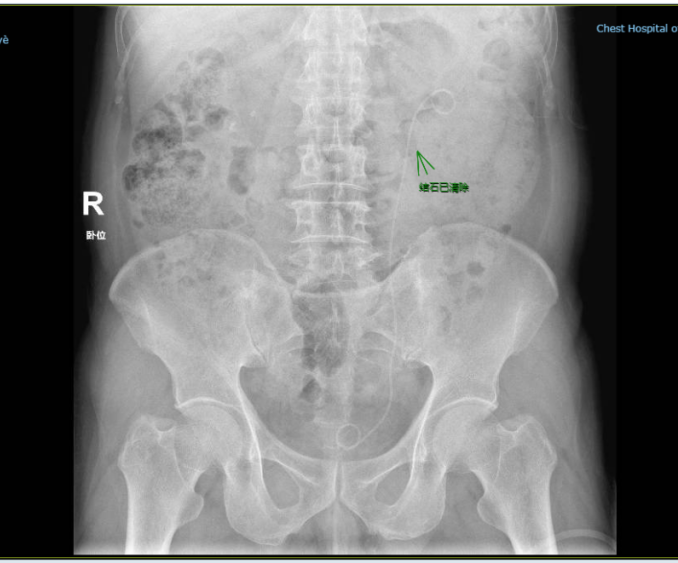

▲术后留管检查,结石已清除